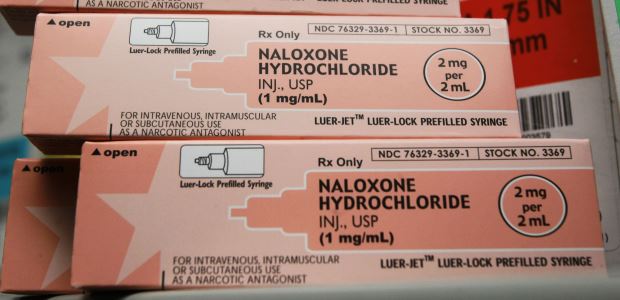

Heroin overdose death rates increased by 26 percent from 2013 to 2014 and have more than tripled since 2010, from 1.0 per 100,000 in 2010 to 3.4 per 100,000 in 2014.